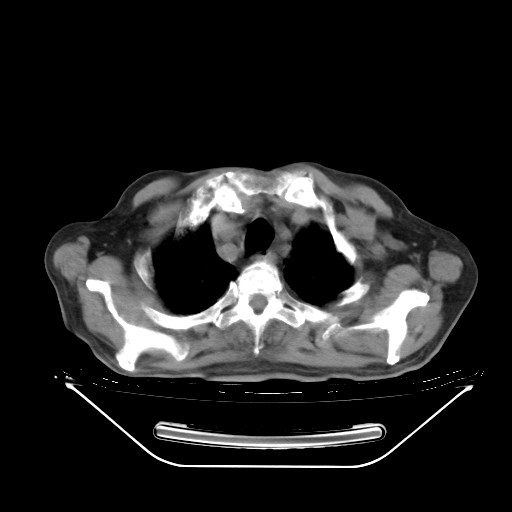

今天复查肺部CT,发现双肺广泛磨玻璃样改变。所以我把3月19日和5月9日相隔50天的肺部CT上传。请大家会诊。

5月9日肺部CT(在4月27日齐鲁医院肺部CT描述部分肺组织磨玻璃样改变,12天后肺组织广泛磨玻璃样改变)

大致读了系列胸部CT:纵隔窗无明显异常,肺窗:从4、27至今:主要是双肺中下野外带可见毛玻璃样改变,目前处于急性肺泡炎阶段,至于原因考虑1、结替组织或胶原血管性疾病所致?2、恶性疾病如恶组在肺部所致的表现或细支气管肺泡癌?3、药物或其它原因如肺蛋白沉着症所致肺泡炎目前不太可能?总之,明天就去请我院的呼吸科、感染科、血液科和临免专家会诊哈。